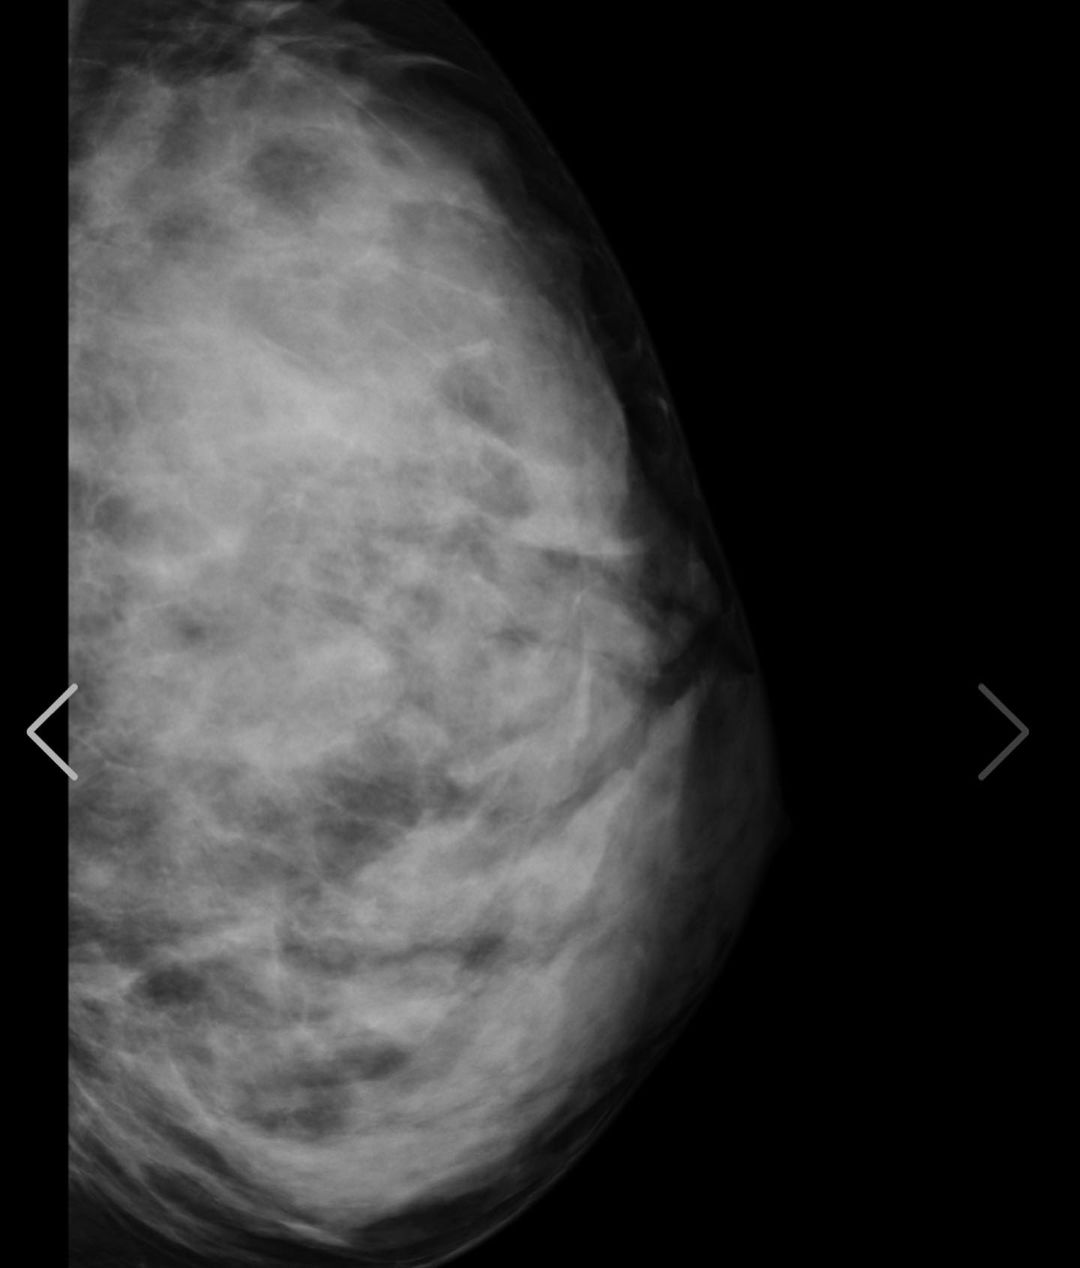

写真は私の胸部レントゲンです!www

裸を通り越して私の骨と脂肪を

見れたあなたには幸運が訪れると

信じてます❤️(私の胸は遺伝です)w